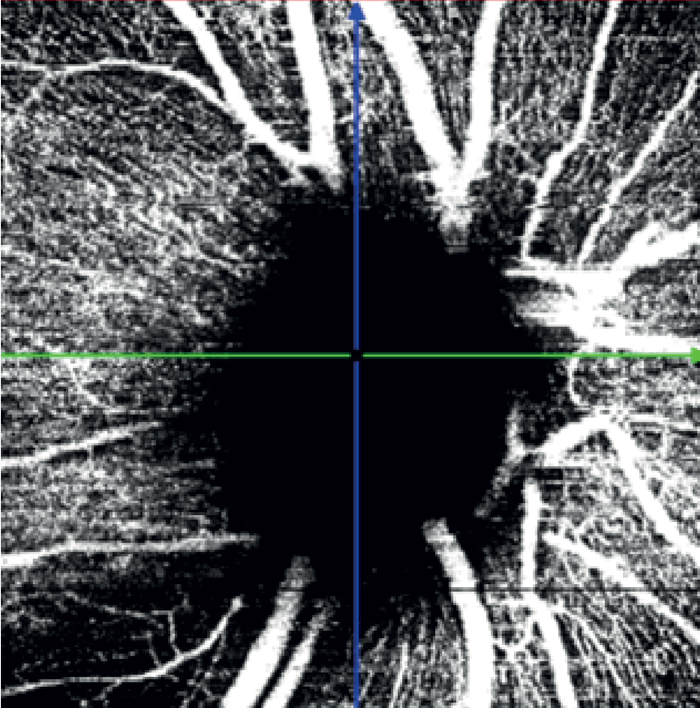

In the left eye – which had a mild inferotemporal RNFL thinning and a normal visual field – SPECTRALIS OCT Angiography revealed a wedge defect and corresponding profound capillary dropout around the optic nerve head (see Figure 8). This corresponded to capillary dropout in the inferior macula (see Figure 9).